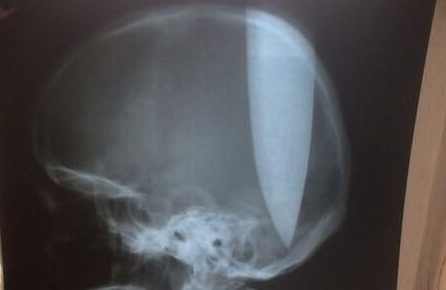

Un hombre se clavó un cuchillo de 20 centímetros en la cabeza para "poder respirar"

Un hombre que aparentemente tiene trastornos psiquiátricos se clavó un cuchillo de 20 centímetros en la cabeza para “poder respirar”.

Ocurrió en la región rusa de Rostov. Según informó el portal Privet Rostov, fue encontrado por automovilistas locales en un campo de la zona. Tenía el cuchillo clavado en la cabeza y estaba totalmente lúcido.

Los médicos pudieron extraerle el cuchillo e informaron que está estable y fuera de peligro. Estará una semana internado en terapia intensiva y después será derivado a una institución psiquiátrica, según RIA Novosti.

Fotos:ArgumentuaLife / Bizon.news